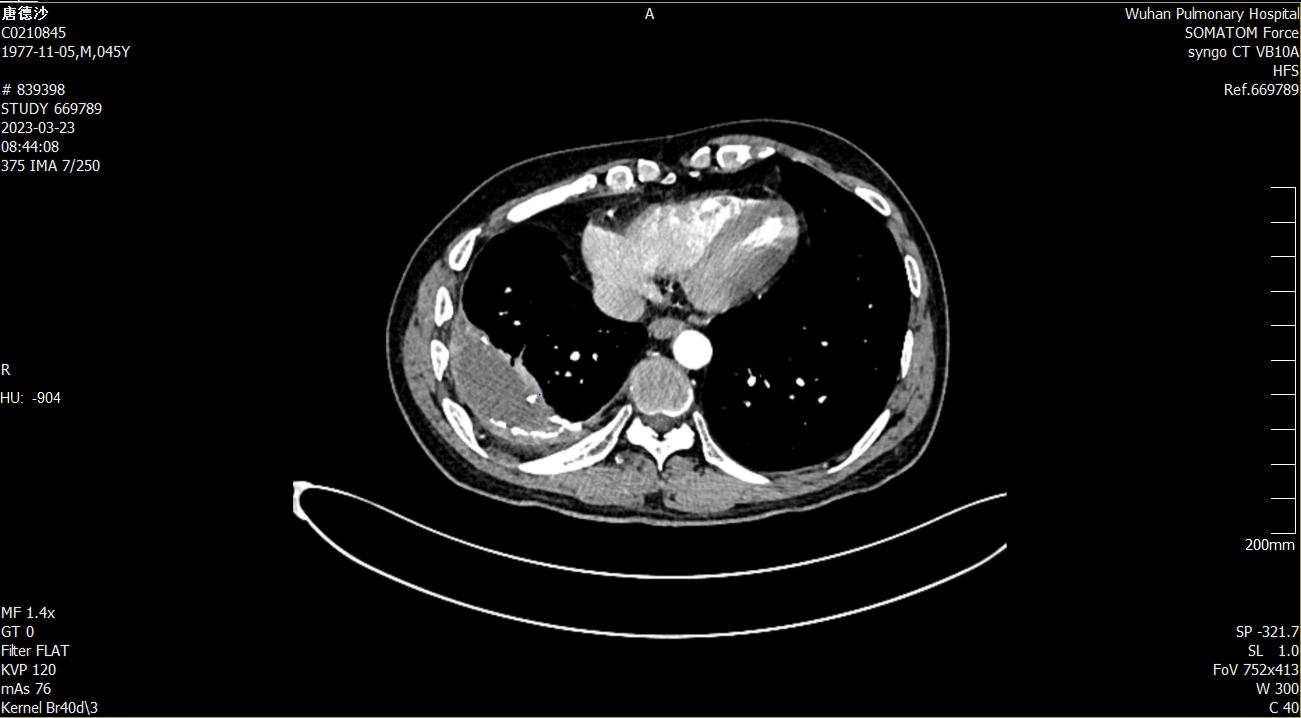

今年 1 月,唐女士开始感觉胸闷、胸痛,稍一活动就气促不已。到她所在省最好的结核病医院进行检查发现,在右肺与胸壁间,结核菌已经筑成一个直径约 10 厘米大小的椭圆形病灶,病灶外壳是钙化了的纤维板,如石头筑起的屋子一般坚硬。「石屋」里面充斥的全是黄绿色脓液,结核菌游弋其中,繁衍生息。

当地医生表示,「石屋」外壳,如铜墙铁壁,需要打断一根肋骨,将胸腔打开,再用咬骨钳拆除。一听到要「开膛」,唐女士惶恐不已,他网上搜索发现,在国内,仅有上海市肺科医院和武汉市肺科医院两家,有不「开膛」就能拆「石屋」的技术,于是,选择了距她最近的武汉市肺科医院。

27 日,唐女士接受了单孔胸腔镜微创治疗结核性脓胸手术。刘奇斌说,结核菌筑起的「石屋」夹在右下肺和右侧胸壁间,且与胸壁、右肺融为一体,只能用咬骨钳一点点地往下剔。靠近右肺的一侧,与右肺几乎没了界限,又硬又牢,稍有不慎就可能伤及右肺,造成气胸。而靠近胸壁的一侧,则与大量血管纠缠,稍有不慎就可能伤及肋间动脉造成大出血。这些都考验着医生运用单孔胸腔镜的娴熟程度和足够的耐心。